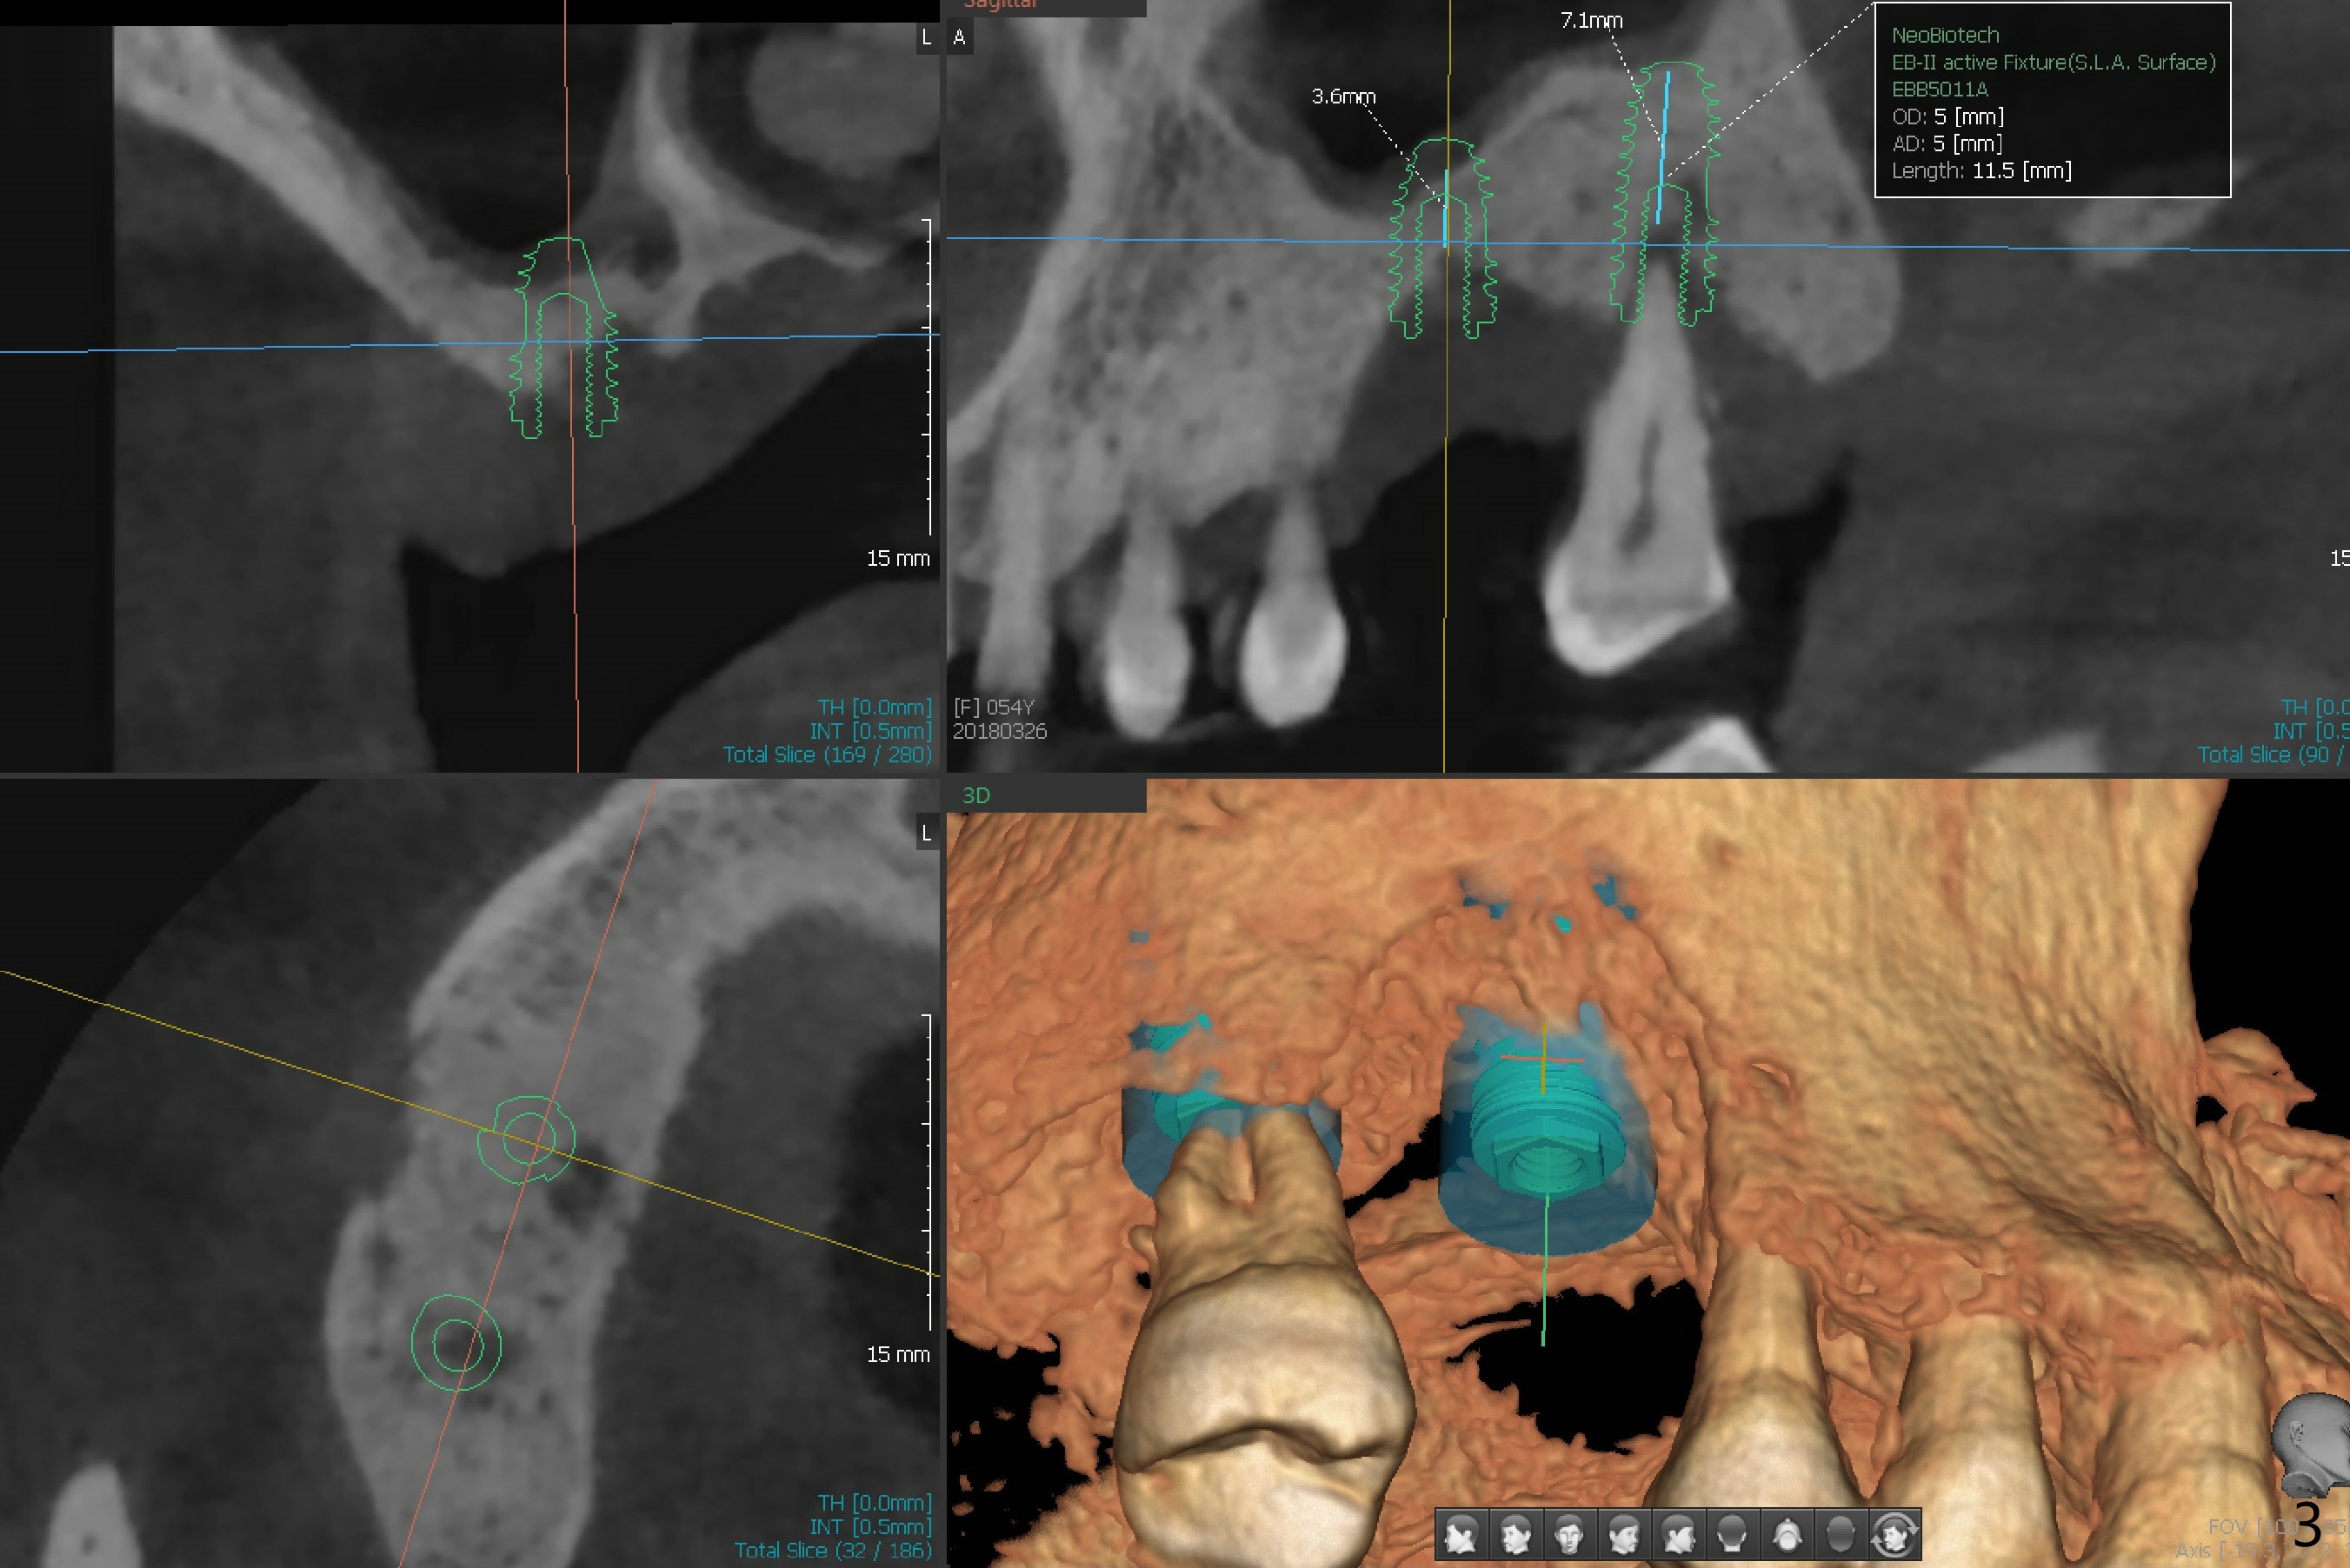

The tooth #2 of a 54-year-old woman has severe bone loss, while #3 has exfoliated (Fig.1). If the former is found without shifting, incision will be made at #3 (and prepare 4 and 6 mm tissue punches), followed by IS drills with 3 mm stoppers until 4.5 mm in diameter (Fig.3). Sinus lift will be accomplished with 3.6 mm round drill from Master Kit with 4-6 mm stoppers, followed by PRF membrane (total 3-4) and Vanilla Graft. Use Prosthetic Planning Kit to choose a proper cementation abutment. The tooth #2 will be extracted. Osteotomy starts with 7 mm stopper (Fig.2,3)...